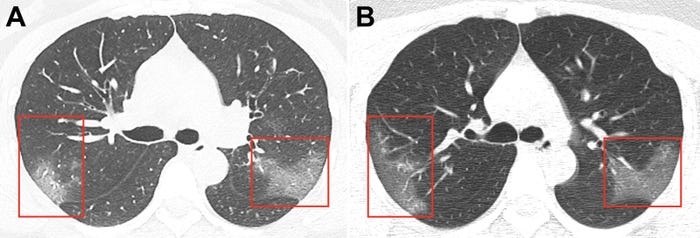

Μια ανησυχητική βλάβη στους πνεύμονες αφήνει, όπως φαίνεται, σε ορισμένους ασθενείς που θεραπεύτηκαν, ο κορονοϊός.

Στην παραπάνω διαπίστωση κατέληξε μια ομάδα γιατρών-ερευνητών από το νοσοκομείο Princess Margaret του Χονγκ Κονγκ, που εξέτασε 12 ανθρώπους, οι οποίοι νόσησαν από τον Covid-19 και τον ξεπέρασαν, καθώς κάποιοι από αυτούς αποδείχθηκε πως είχαν περιορισμένη χωρητικότητα πνευμόνων κατά 20 μέχρι 30%, μετά την ανάρρωσή τους, όπως μεταδίδει το businessinsider.com.

Σύμφωνα πάντα με την έρευνα από το Χονγκ Κονγκ, ότι οι συγκεκριμένοι άνθρωποι κινδυνεύουν να αναπτύξουν πνευμονική ίνωση: Μια κατάσταση, που χαρακτηρίζεται από τη σκλήρυνση του πνευμονικού ιστού, και εμποδίζει τα αναπνευστικά όργανα να λειτουργούν σωστά.